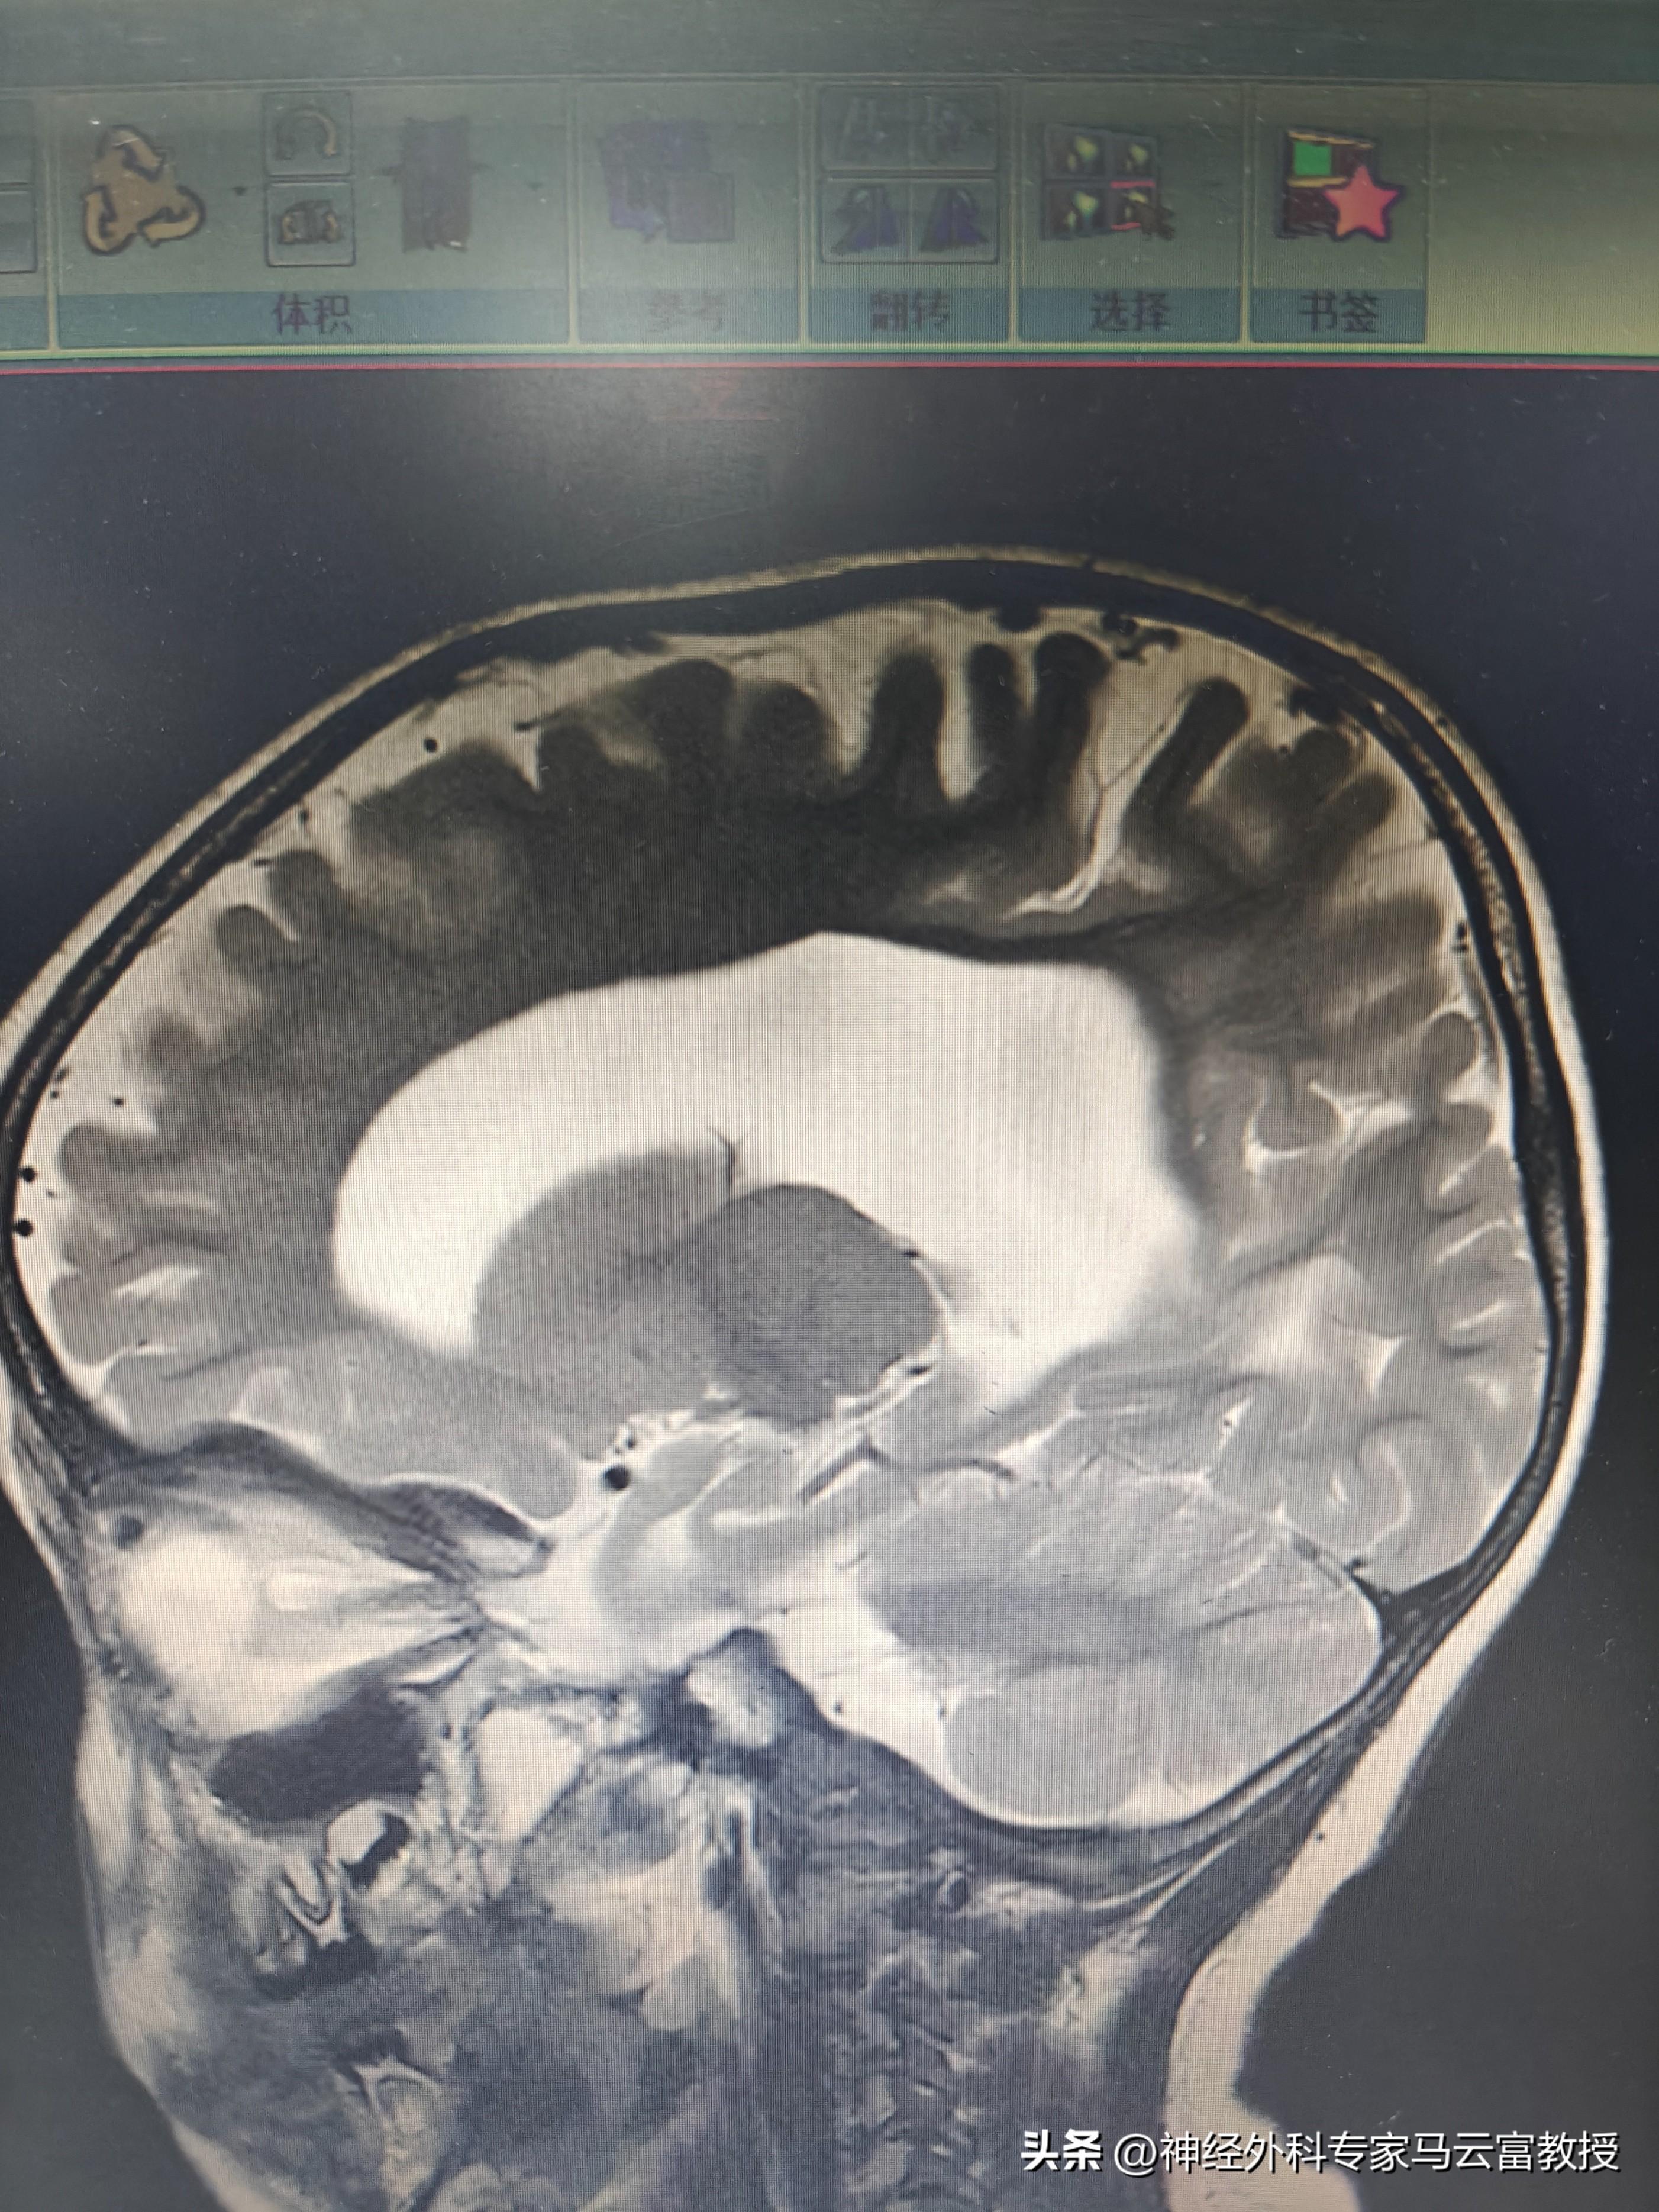

孩子頭圍已達57cm(遠超同齡正常水平),發育也明顯滯後,目前僅能發出 “爸爸”“媽媽” 的簡單音節。在當地醫院檢查時,醫生髮現寶寶側腦室正在逐漸增寬,建議立即轉診至我院進一步診治。

我院神經外科馬雲富主任接診後,通過細緻查體與顱腦 CT 檢查,明確診斷爲幕上腦積水。入院後,團隊完善了腦 MRI + 腦脊液電影成像等精準檢查,最終判斷爲不全梗阻性腦積水,且腰穿提示腦室內壓力不高。綜合評估後,馬雲富主任爲患兒制定了腦室 - 腹腔分流術的治療方案,爲寶寶的大腦 “減壓”,重啓正常發育的可能。